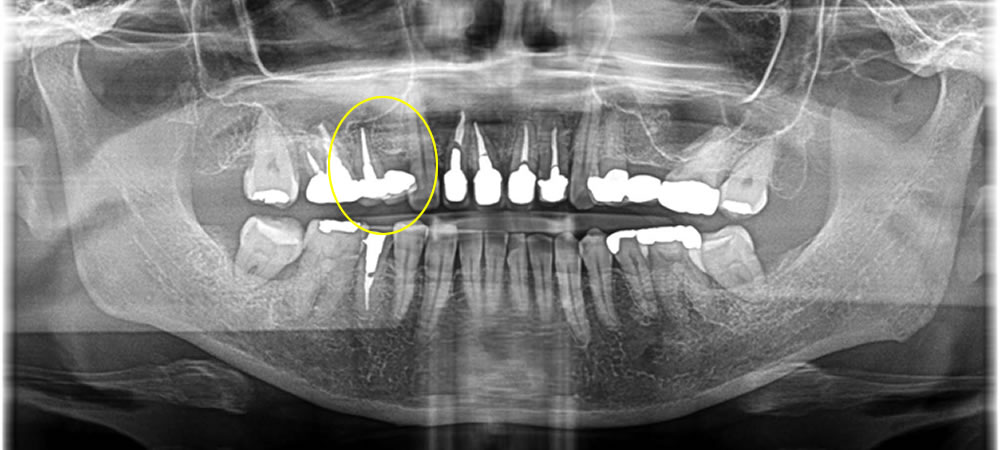

延長ブリッジ部分をインプラントで治療した症例

こちらの患者さまは過去に延長ブリッジを他院にて装着している所にインプラントを希望され来院されました。

骨がしっかりとある事をCTにて確認する事ができたので、今回は切開を7ミリに抑え低侵襲でオペを行いました。